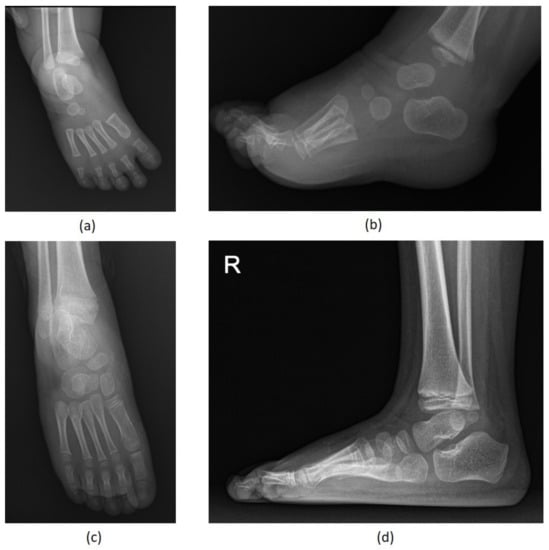

| Patient Number | Affected Foot | Preoperative Anteroposterior Talocalcaneal Angle (°) | Preoperative Lateral Talocalcaneal Angle (°) | Anteroposterior Talocalcaneal Angle at Final Follow-Up (°) | Lateral Talocalcaneal Angle at Final Follow-Up (°) |

|---|---|---|---|---|---|

| 1 | Right | 20.8 | 22.2 | 30.4 | 37.2 |

| 2 | Right | 24.2 | 26.9 | 30.5 | 26.9 |

| Left | 26.1 | 27.0 | 31.4 | 27.6 | |

| 3 | Left | 27.0 | 1.0 | 32.9 | 27.6 |

| 4 | Right | 8.7 | 17.8 | 30.8 | 32.8 |

| Left | 22.1 | 24.8 | 31.7 | 26.8 | |

| 5 | Left | 15.9 | 18.7 | 30.9 | 26.5 |

| 6 | Right | 28.8 | 23.4 | 31.9 | 25.8 |

| Left | 25.8 | 34.1 | 32.5 | 25.4 | |

| 7 | Right | 20.2 | 29.3 | 34.4 | 33.9 |

| Left | 16.8 | 38.4 | 33.4 | 39.1 | |

| 8 | Right | 32.4 | 30.8 | 33.9 | 38.1 |